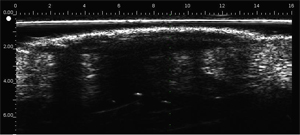

Seborrhoeic wart

Posterior attenuation in the dermis due to prominent entry echo (heavily keratinized tumour).